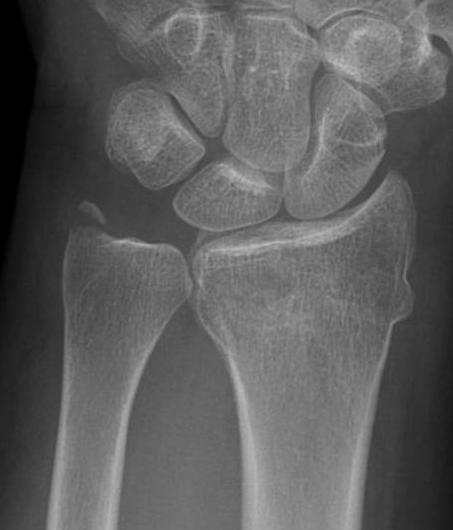

Xray

True lateral

- radial styloid overlies proximal scaphoid / lunate / triquetram

Dorsal subluxation of the distal ulna